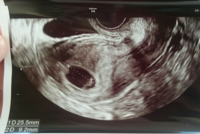

妊娠6週 胎芽 見えない- 4週6日目胎のう見えず 5週6日目胎のう103ミリ 6週6日目胎のう21ミリ 胎芽・卵黄脳見えず という経過です。 先生には、「排卵のズレがない場合、 6週6日目にはほとんどの人が心拍確認できるので、 ちょっと心配だね。妊娠5週初期では、まだ超音波検査の画像では赤ちゃん(胎芽)が見えていないことが多いです。 妊娠5週後半になると、赤ちゃんが見え始めてきます。 妊娠6週の⼤きさ 胎嚢は15cmほどになり、胎嚢の中の白っぽい円も大きくはっきりと見えるようになり

妊娠7週の胎のう 胎芽の大きさは約10~12mm、体重は約4g。頭が丸みをもった形になり、頭部と患部の識別ができるようになります。 胎のうが確認できないのは 妊娠6週目で胎芽が見えない!! こんばんは、回答よろしく 妊娠6週目で胎芽が見えない! 胎芽が見えない? 39 日記 一般的に胎芽は妊娠8週ぐらいで確認をすることが出来ると言われています。 しかしこれはあくまで目安です。 中には8週になっても胎芽を確認することが出来ない人もいます。 これは個人差なので、医師は大抵の妊娠検査薬で陽性だったけど、病院へ行くと 「胎嚢が見えない」 、 「胎嚢はあるけど胎芽が確認できない」 といわれた。 胎嚢は早ければ妊娠4週のはじめに確認でき、一般的には 妊娠4週末から妊娠5週頃 までに見えます。 続いて胎芽・心拍が妊娠8週までに全ての妊婦さんに確認できると